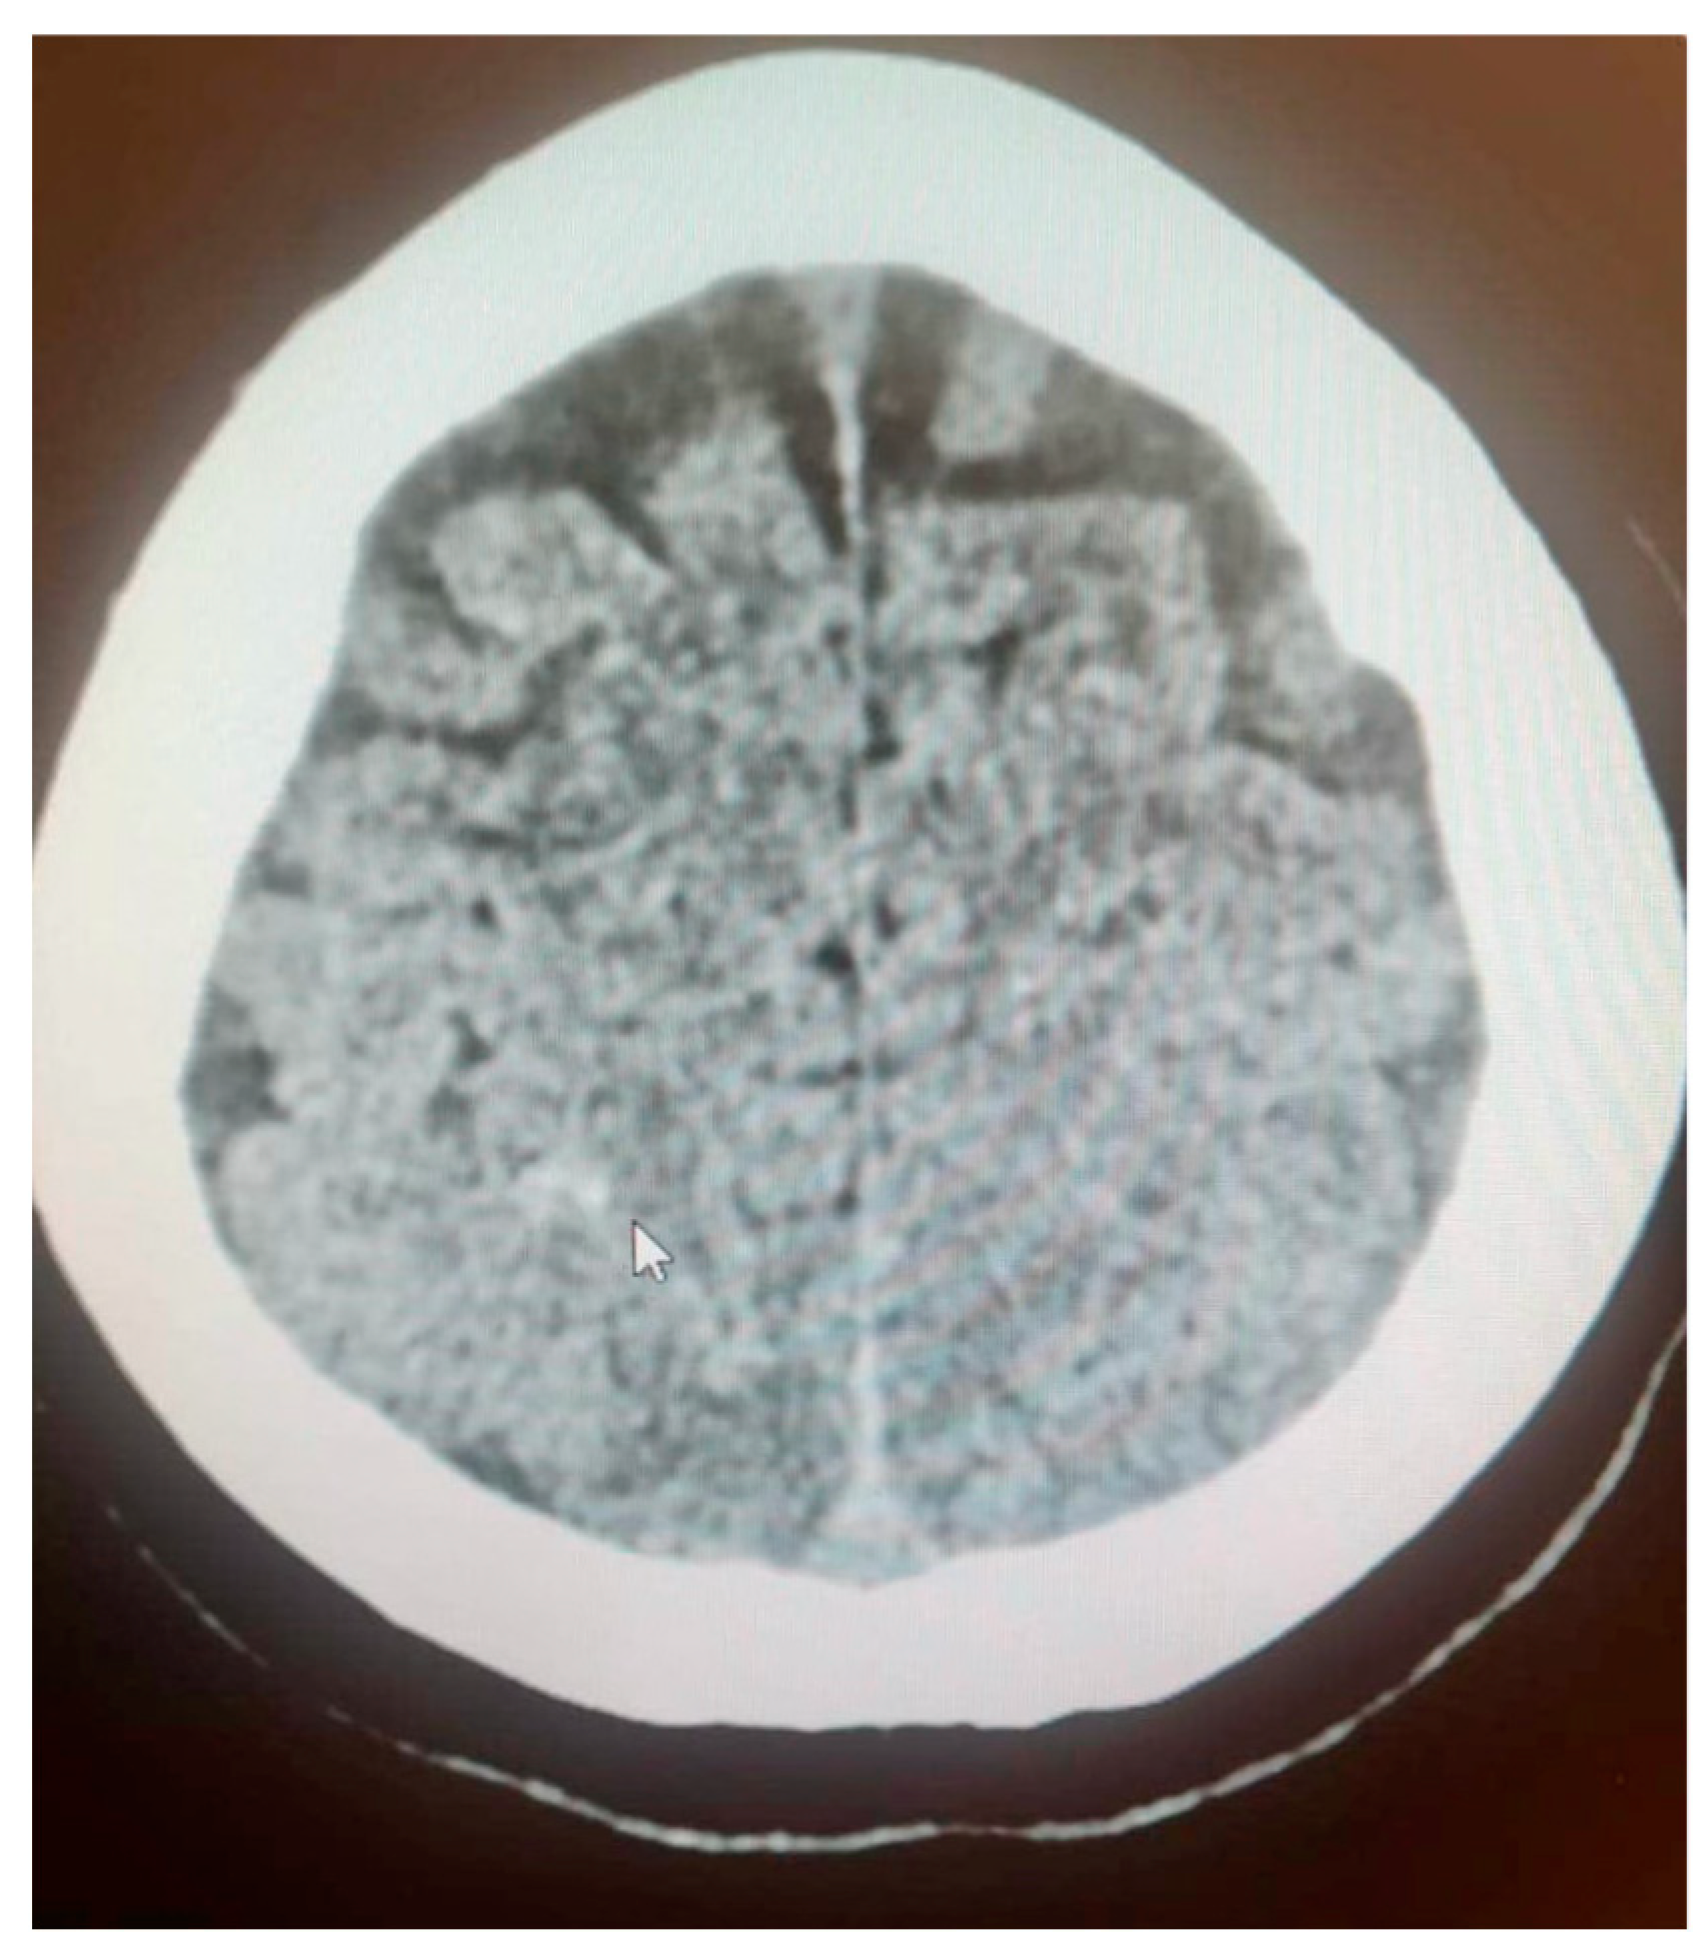

The patient was transferred to the postoperative intensive care unit (ICU) in a serious general condition. A control CT of the brain confirmed cerebral edema, areas of hypodensity and SAH (Figure 2). An angio-chest CT revealed a small amount of fluid in both pleural cavities, up to 12 mm. Areas of parenchymal consolidation were visible bilaterally in the dorsal parts of the lungs, partially with an air bronchogram, which may correspond to atelectatic inflammatory changes. No signs of pulmonary embolism were found. An echocardiogram was performed, which showed good global left ventricle contractility, an estimated eviction fraction of 50%, and no signs of cardiopulmonary overload; as well, it found significant symmetrical hypertrophy of the cardia (14 mm) and traces of aortic insufficiency. An abdominal CT revealed an enlarged liver and a small amount of free fluid in the pelvis (Figure 3). Following the scans, the patient was transferred to an obstetrics operation theater, where an immediate cesarean section was performed due to high risk of maternal mortality, delivering an extremely immature, low-weight fetus. Regardless of the highest level of neontological care, fetal resuscitation procedures were abandoned, palliative care was provided and fetal death was confirmed within 2 h.

Figure 2. Brain CT confirmed cerebral edema, areas of hypodensity and SAH (white arrow).